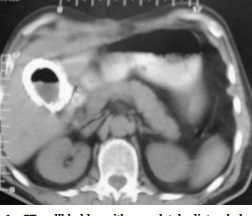

This belongs to a patient that I operated with closed method due to gallbladder inflammation. The wall of the bladder is edematous and the wall thickness is increased.

Calcification in the wall of the gallbladder and porcelain gallbladder are seen on the tomography.